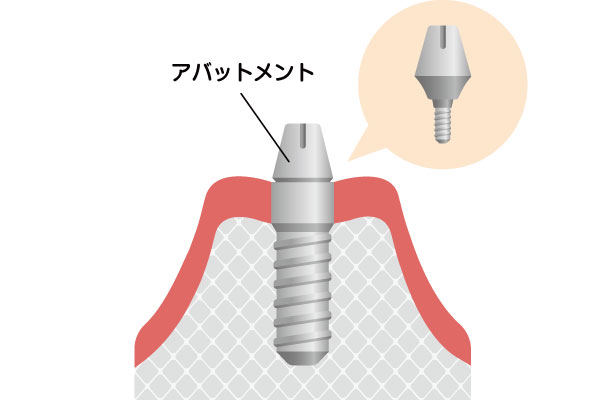

インプラントは、歯を失った部分のあごの骨に、チタンまたはチタン合金製の人工歯根を埋め込み、それを土台として人工の歯を装着する治療です。チタンは、骨としっかり結合する性質があり、生体親和性にも優れた材質です。インプラントは、人工歯根(インプラント体)、土台(アバットメント)、人工歯(上部構造)という3つの構造から成り立っており、審美的に良好なだけではなく、周囲の歯に負担をかけることなく、しっかりと噛む機能を取り戻します。

アバットメント(土台)の接続

インプラントと骨の結合が確認できたら、インプラントにアバットメント(土台)を接続するための二次手術を行います。